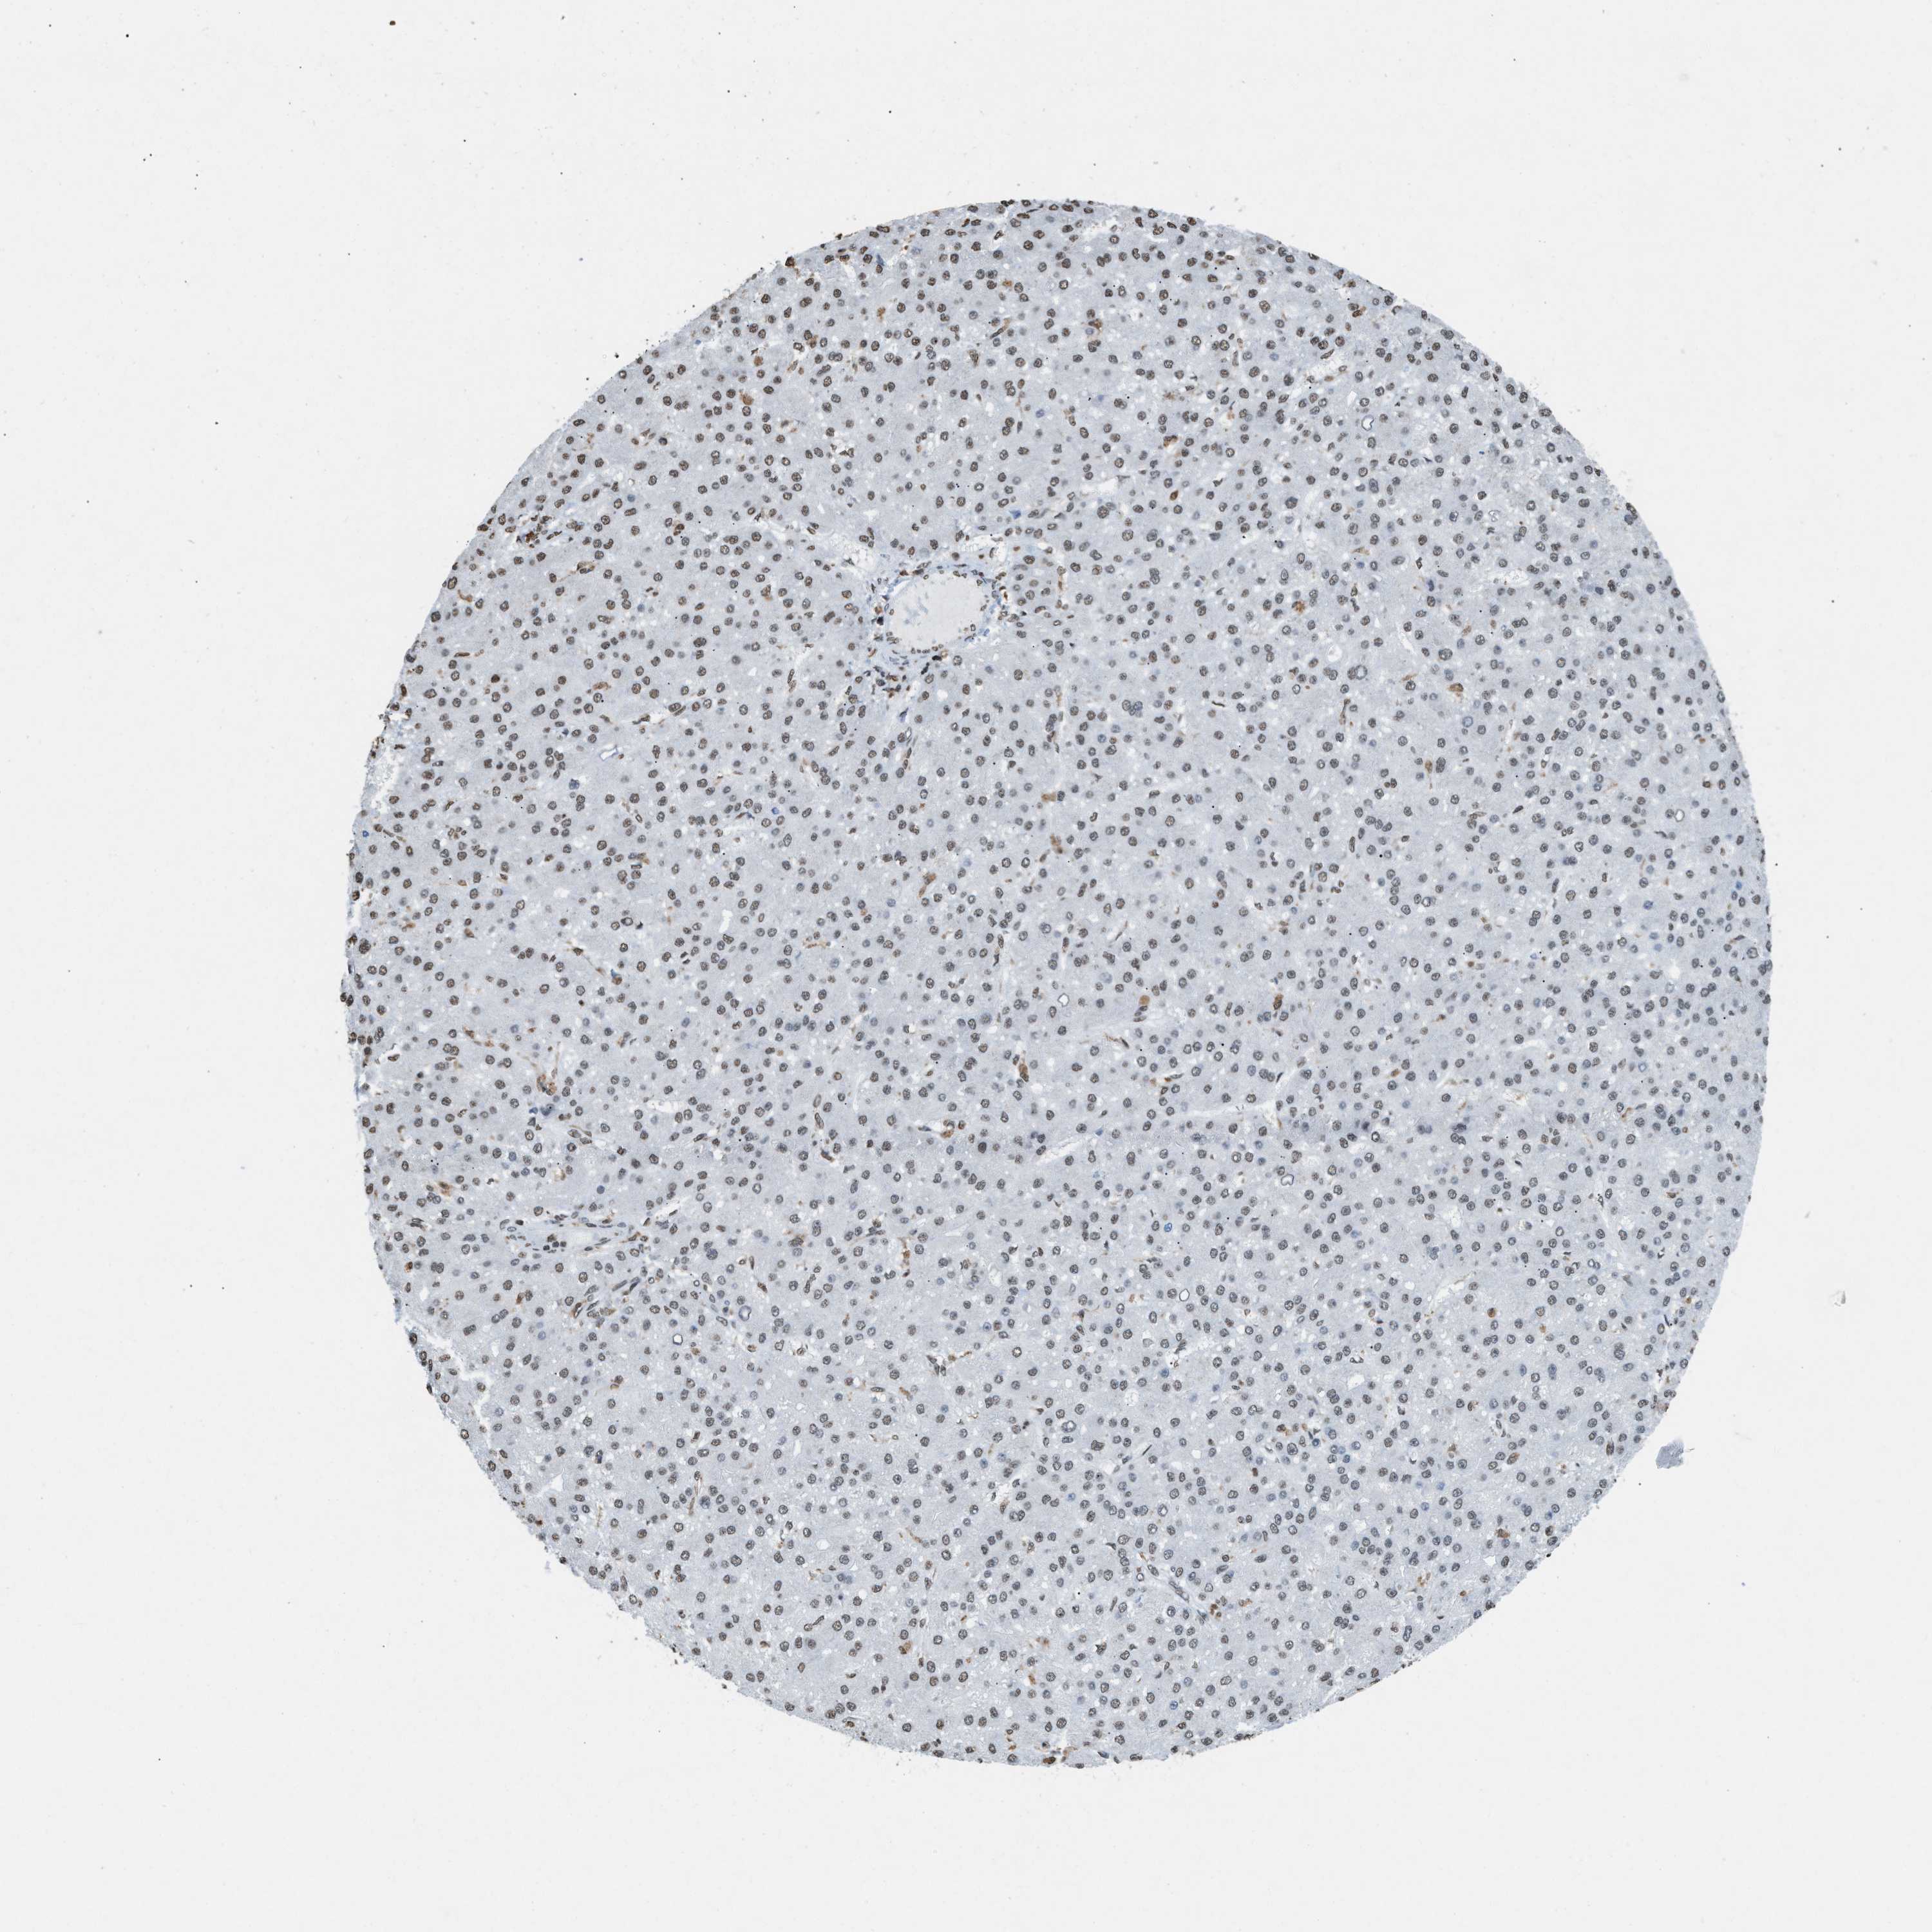

LIVER CANCER - Protein expressioni

A mouse-over function shows sample information and annotation data. Click on an image to view it in a full screen mode. Samples can be filtered based on level of antibody staining by selecting one or several of the following categories: high, medium, low and not detected. The assay and annotation is described here.

Note that samples used for immunohistochemistry by the Human Protein Atlas do not correspond to samples in the TCGA dataset.

Antibody stainingi

Antibody staining in the annotated cell types in the current human tissue is reported as not detected, low, medium, or high, based on conventional immunohistochemistry profiling in selected tissues. This score is based on the combination of the staining intensity and fraction of stained cells.

Each image is clickable and will lead to virtual microscopy that enables deeper exploration of all samples and also displays staining intensity scores, fraction scores and subcellular localization as well as patient and tissue information for each sample.

Antibody HPA021816

Antibody CAB002209

Staining

High

Medium

Low

Not detected

Intensity

Strong

Moderate

Weak

Negative

Quantity

>75%

75%-25%

<25%

None

Location

Nuclear

Cytoplasmic/membranous

Cytoplasmic/membranous,nuclear

Cholangiocarcinoma

Carcinoma, Hepatocellular, NOS